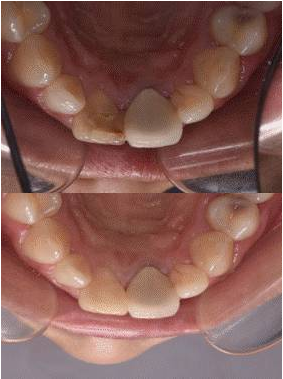

11去除暫封材料,清理髓腔,選擇性釉質(zhì)酸蝕,涂自酸蝕粘結(jié)劑,牙本質(zhì)色樹脂充填牙本質(zhì)層,牙釉質(zhì)色樹脂充填釉質(zhì)層,調(diào)牙合修形,拋光。圖10[1]/11/12(停止漂白后,需等待2周以上[2],以使顏色穩(wěn)定、氧氣消散及恢復(fù)粘結(jié)力,若患者時間緊迫,為了中和過氧化物的氧化性,也可用過氧化氫酶沖洗髓腔,或應(yīng)用氫氧化鈣覆蓋髓腔2天)

圖11 治療后唇側(cè)觀

圖12 治療后舌側(cè)觀

圖13 治療前后唇面對比

圖14 治療前后舌側(cè)對比